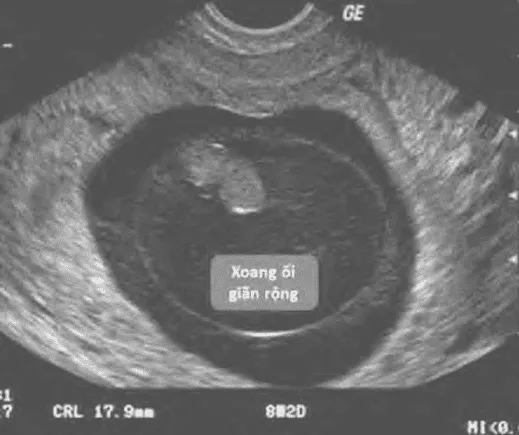

- Xoang ối giãn rộng (expanded amnion sign).

Triệu chứng ra máu, đau bụng, cổ tử cung đóng. Dấu hiệu siêu âm dự báo (không khẳng định) bao gồm:

- (MSD - CRL) < 5 mm.